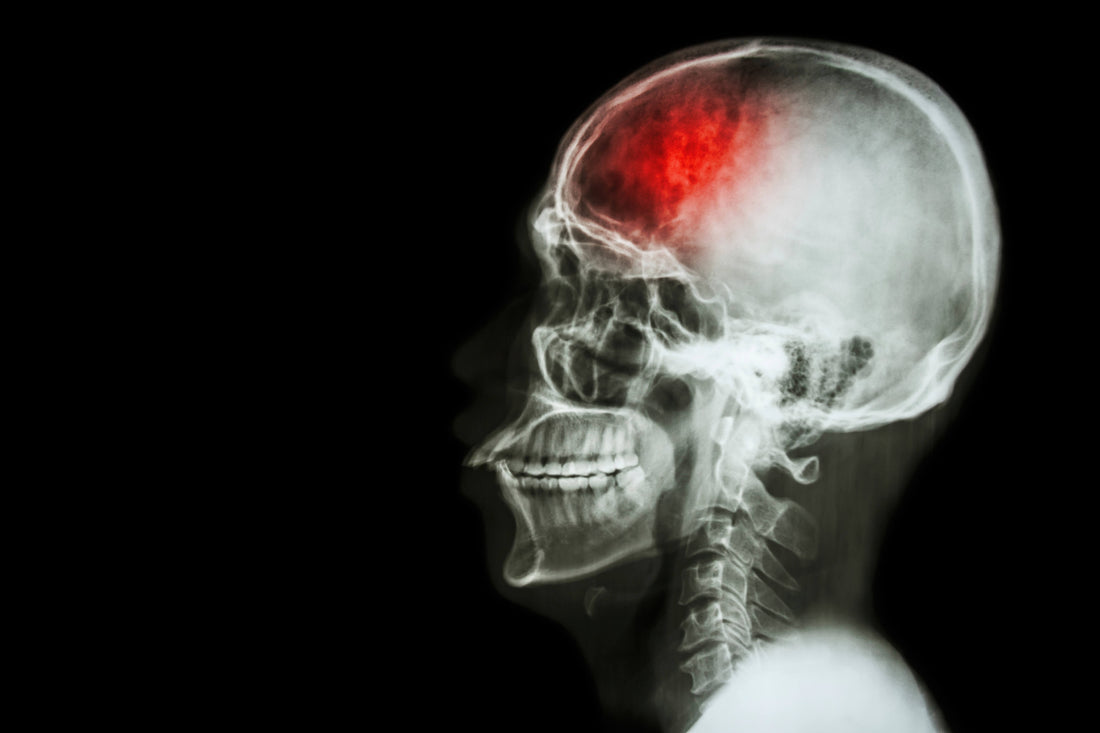

Today, it is generally believed that eating a lot of fiber helps prevent obesity, diabetes, and cardiovascular diseases like stroke. Strokes are the second most common cause of death worldwide and the leading cause of disability in many developed countries. So preventing strokes in the first place should be a key public health priority.

Strokes are one of the complications ofarterial stiffness.But it doesn't happen instantly. Someone might have a stroke in their 50s, but their arteries were stiffening for decades leading up to the stroke.